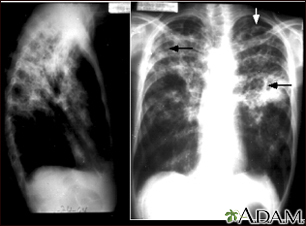

Tuberculosis is an infectious disease that causes inflammation, the formation of tubercles and other growths within tissue, and can cause tissue death. These chest x-rays show advanced pulmonary tuberculosis. There are multiple light areas (opacities) of varying size that run together (coalesce). Arrows indicate the location of cavities within these light areas. The x-ray on the left clearly shows that the opacities are located in the upper area of the lungs toward the back. The appearance is typical for chronic pulmonary tuberculosis but may also occur with chronic pulmonary histiocytosis and chronic pulmonary coccidioidomycosis. Pulmonary tuberculosis is making a comeback with new resistant strains that are difficult to treat. Pulmonary tuberculosis is the most common form of the disease, but other organs can be infected.